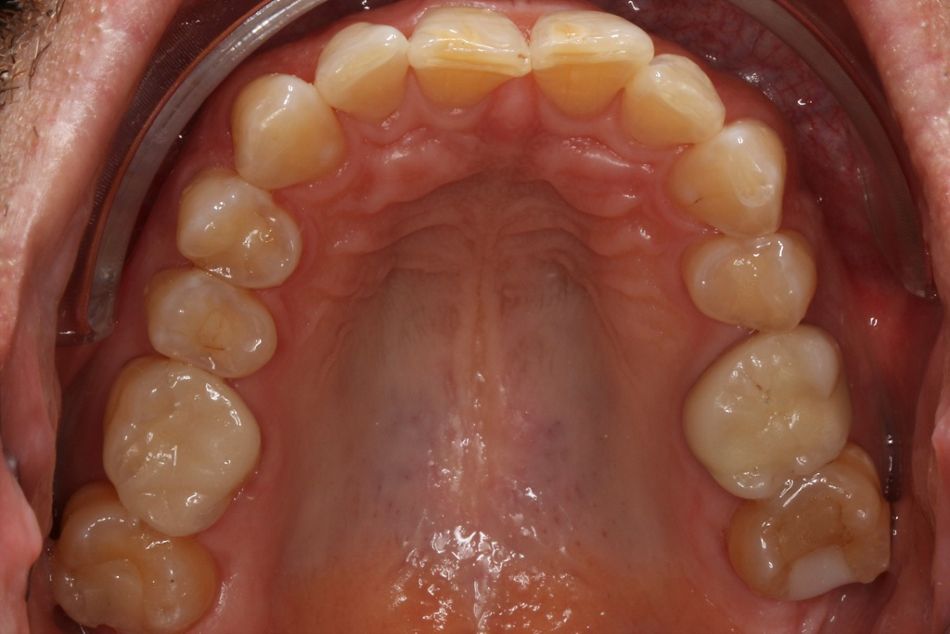

Ausgangssituation

Der Patient stellte sich mit den folgenden Symptomen vor: Er beschrieb das Gefühl, nicht genug Platz für seinen Unterkiefer in der sagittalen Ebene zu haben und hatte sich angewöhnt seine Unterkieferfront stetig gegen die Oberkieferfront zu drücken. Dies beschrieb er als “sehr unangenehm und anstrengend”. Bei Palpation war der M. masseter druckdolent, hypertroph und erhärtet. Die aktive Mundöffnung lag bei 38mm. Passiv ließ sich das auf 42mm erweitern. Es gab statische Frontzahnkontakte in zentrischer Relation. Die Inklination der Oberkiefer Incisivi war größer als 90° im Verhältnis zur Okklusionsebene. Es war schon eine deutliche Attrition im Bereich der Schneidekanten der Oberkieferfront, sowie eine Protrusion der Unterkieferincisivi aufgrund von tertiärem Engstand zu verzeichnen.

Foto Status vor Behandlung